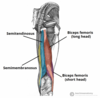

What is this muscle?

What is this muscle?